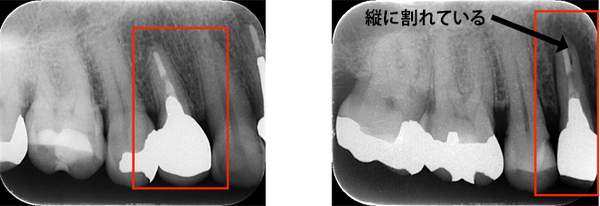

左のレントゲンでは破折したかどうかはわからないが、虫歯になっている部分をとっていくと歯が割れているのがはっきりとわかりました。

こちらの写真は違和感があるということでレントゲンを撮ったが異常は見つからなかった。しかし、1ヶ月後にもう一度撮影すると、歯が割れているのがわかりました。また、歯の周りの骨の部分がやや黒くなっているのも分かります。

ブリッジが取れたということでご来院患者様でした。レントゲンを撮ると縦に割れていました。

破折に気づいてからは、抜歯を行い、インプラントを入れてまた噛める様にしていきました。レントゲンでも破折がわからない時があります。そんな時はCTやマイクロスコープを使うとわかることが多いのです。